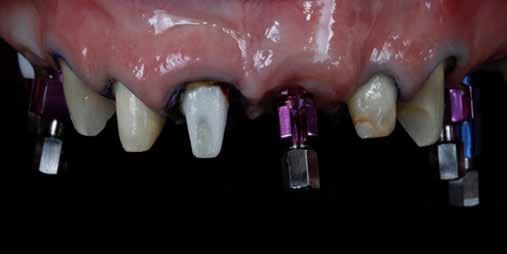

A 26 éves férfi páciens azzal a kéréssel kereste fel a rendelőnket, hogy a frontfogai esztétikusabb megjelenését szeretné elérni. A páciens jó általános egészségi állapottal rendelkezett, nem szenvedett allergiáktól és nem kellett rendszeresen gyógyszereket szednie. A páciens lehetőség szerint kerülte a fogai megmutatását. Rendkívül zavarónak találta a nagymetszői között, a középvonalnak megfelelően látható rést, a fogain látható kopási jeleket, valamint a fogai méretét is túl kicsinek találta. A szájüregi vizsgálat során megállapítottuk, hogy a nagymetsző fogai (11, 21) élharapásban vannak, valamint az alsó fogíven kismértékű torlódást észleltünk. A felső frontfogakon

(13-23) attrícióra utaló jeleket találtunk. A fogak kopása a nagymetszőfogaknak megfelelően volt a legkifejezettebb (1. ábra) . Az előbbiekben említett fogak (11, 21) ezen kívül némileg elfordultak, és jelentősebb méretű diasztéma volt köztük. A páciens Angle I.-osztályú állcsontrelációs helyzettel rendelkezett. A vizsgálat során feltűnt, hogy a páciens csak nagyon óvatosan mert mosolyogni (2. ábra)

A szájüregi vizsgálat során nem találtunk szuvas léziók jelenlétére utaló eltéréseket. A nagymetszőfogakon megfigyelhető jelentős mértékű kopás ellenére nem észleltünk craniomandibuláris diszfunkció jelenlétére utaló jeleket. A vizsgálat befejezését követően a pácienst tájékoztattuk a különböző kezelési lehetőségekről. Az esztétikai megjelenés javítása érdekében először egy alignerekkel végzett fogszabályzó kezelés elvégzését, majd a harapási helyzet optimalizálását követően a felső frontfogai kompozittal történő direkt felépítését vagy héjakkal történő ellátását (pl.: non-prep héjak) javasoltuk (3. és 4. ábra).

A fogazat minimálinvazív módon készített héjakkal történő ellátásához a fogaknak olyan pozícióban kell lenniük, amely lehetővé teszi az esztétikai megjelenés additív eljárások alkalmazása mellett történő optimalizálását.1. ábra: Kiindulási állapot. A felső nagymetszőfogak élharapásban vannak. 2. ábra: Az orthodonciai kezelés megkezdése előtt készített intraorális felvétel. A páciens csak óvatosan mer mosolyogni. 3. és 4. ábra: Digitálisan megtervezett kezelés.

A kezelések második fázisában a pácienssel közösen non-prep/ minimálinvazív héjak készítése mellett döntöttünk (6. és 7. ábra).